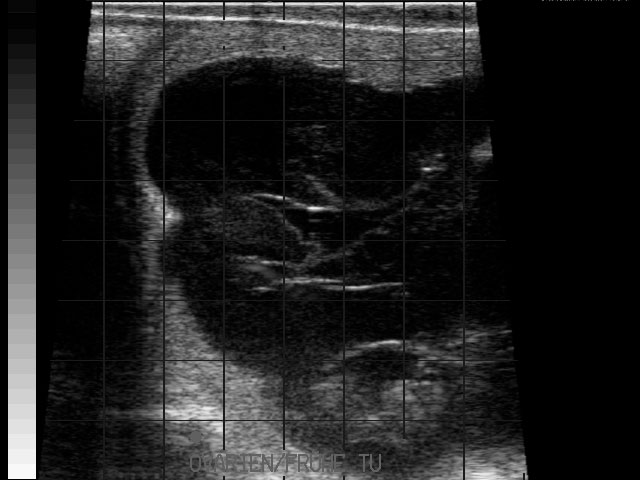

Eierstockstumor

Frühe Resorption